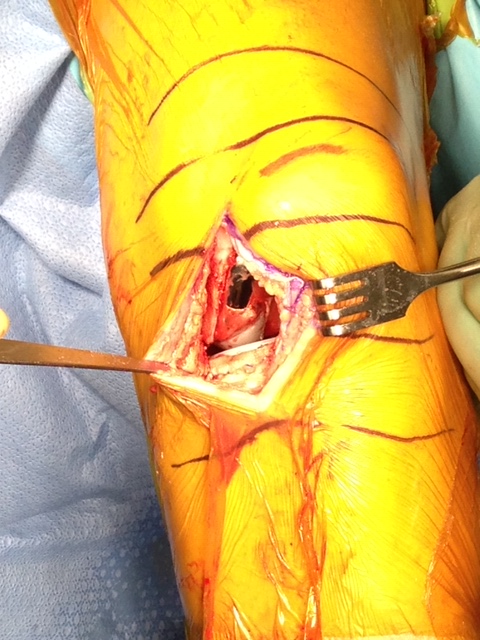

Here are some pictures of what unicompartmental arthritis looks like